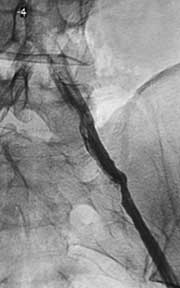

Рис. 1. Атеросклероз брюшной аорты и ее ветвей.